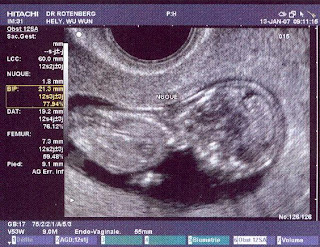

Seri Hamil: Premier Echographie

tanggal 13 januari kemaren hari bersejarah buat dirikuw.

itu kali pertama echographie atau sering disebut di indo sono sebagai usg. berhubung mengalami hamilnya juga baru sekarang, ya itu pertama usg dan pertama melihat si jabang bayi di layar ruang dokter itu.

setelah melalu masa penantian yang cukup panjang. minta janji ketemu aja 3 minggu. sempet ditolak si dokter karena minta lebih cepet dari tanggal itu. kata doski, usg pertama harus lebih dari 2 bulan 2 minggu. sepertinya di negara lain nggak musti selama itu ya.. tapi yang sutralah, lah namanya idup disini kok.

moment ini moment penting. pertama, karena bisa memastikan apakah si janin itu nyata adanya dan mengecek bagaimana kondisinya. kedua, lihat yang pertama.

so, mengingat sejak awal dicurigai hamil, sayanya cuman tes darah sekali, dan nol kali ditangani dokter (disini emang dicuekin sampe memasuki pertengahan bulan ke 2). saya yang cuman mengandalkan internet dan satu buku soal kehamilan serta tanya kiri kanan. berjuang keras hidup sesehat mungkin dan semaksimal mungkin buat si jabang bayi.. tapi namanya emak emak hamil, ya cemas mulu.. takut inilah takut itulah. yang paling ditakutin kalo ternyata si jabang bayi fiktif adanya. cuman menyumbang mual mual dan capek yang nggak masuk akal. apalagi, kalo liat perut, kok masih segitu aje. bukan kayak orang hamilton gitu.

jadi sabtu itu. saya dan suami bangun 20 menit lebih pagi dari biasanya. haha perhitungan banget! terus bergegas ke dokter. eh dianya lagi ngetok ngetok dinding. kagak menenangkan banget. terus dia suruh kita masuk ruangan. namanya amatiran, kita masuk ke ruangan yang isinya tempat tidur dari besi, dan berbagai peralatan ronsen yang gede gede. wuih, udah jiper aja tuh berdua, apalagi saya. taunya, salah ruangan! hehe.

di dalem ruangan, perut saya diolesin sama krim gitu, dan mulai lah deteksi si jabang bayi. terus ,munculah dia dilayar. persis kayak yang majalah dan buku. dengan warna item putih, di udah keliatan lengkap. malah si dokter bisa bilang: ini tangannya 2, kakinya 2, jarinya 3 (belom jadi kali yang laen hehe), perut, jantung, kepala, tulang belakang.. etc etc, sayanya sambil denger sambil mau nangis.. terharu banget! sampe napas turun naik. bayi saya panjangnya 7 cm. terus, si dokter kasih denger bunyi, duk duk duk duk.. itu bunyi detak jantungnya. Ah, nahan nangisnya tambah susah.. saat itu saya sadar, kalo di badan saya sekarang ada 2 detak jantung.. suami saya yang sambil berdiri, saya tengok juga tersenyum terharu.

juga ketika ada alat yang masuk ke dalam bagian intim saya. seperti kehilangan virginitas dua kali. biar rasanya aneh, saya pasrah. demi si detak jantung yang satu lagi itu.. kata si dokter, semua baik baik saja :-)